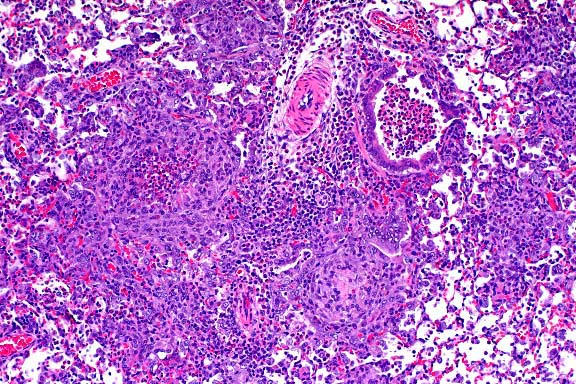

- Case 19-1. Lung. Multifocally throughout the lung,

abundant macrophages, eosinophils, neutrophils and scattered

foreign body or Langhans giant cells expand or replace alveoli

and bronchioles.

- Contributor's Diagnosis and Comments: Lung: Peribronchiolar

and interstitial pneumonia, granulomatous and eosinophilic, multifocal

(varied severity among sections).

Multifocally throughout the lung there are variably-sized, discrete,

noncaseating granulomas, mostly arranged around bronchioles,

but also present around or adjacent to vessels in the interstitium.

Granulomas are usually composed of tightly packed epithelioid

macrophages admixed with frequent multinucleated, Langhans-type

and foreign body-type giant cells and mild to moderate numbers

of eosinophils and neutrophils. Within granulomas, there are

occasional small central areas of necrosis characterized by accumulation

of cellular and nuclear debris, degenerate polymorphonuclear

leukocytes, and rarely, deposition of small amounts of brightly

eosinophilic, club-shaped, amorphous material (Splendore-Hoeppli

material; not present in all sections). In addition, throughout

the interstitium there are small to conspicuous perivascular

cuffs composed mostly of eosinophils and neutrophils, admixed

with occasional lymphocytes. In association with inflammatory

infiltrates, there is also mild to moderate alveolar histiocytosis,

mild to moderate interstitial edema, mild thickening of alveolar

walls with type II pneumocyte hyperplasia, and mild to moderate

hyperplasia of bronchiolar epithelia with mucous metaplasia.

- AFIP Diagnosis: Lung: Pneumonia, granulomatous and

eosinophilic, peribronchiolar and perivascular, multifocal, moderate,

with perivascular edema, Brown Norway rat, rodent.

- Conference Note: Like the contributor, participants

identified perivascular and peribronchiolar inflammatory infiltrates

composed of macrophages with multinucleate giant cells and eosinophils,

and fewer lymphocytes and plasma cells. Inflammatory cells expand

adjacent alveolar septa, and sometimes obscure or fill alveoli,